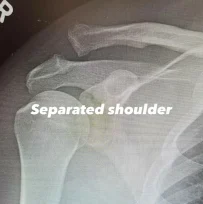

Η πρώτη του ανάρτηση περιλάμβανε μια ακτινογραφία του ώμου του, όπου απεικονίζονταν καθαρά δύο σπασμένα οστά.

«Αποκόλληση ώμου», έγραφε, ακολουθούμενη από μια δεύτερη, μετεγχειρητική φωτογραφία του ίδιου σημείου.